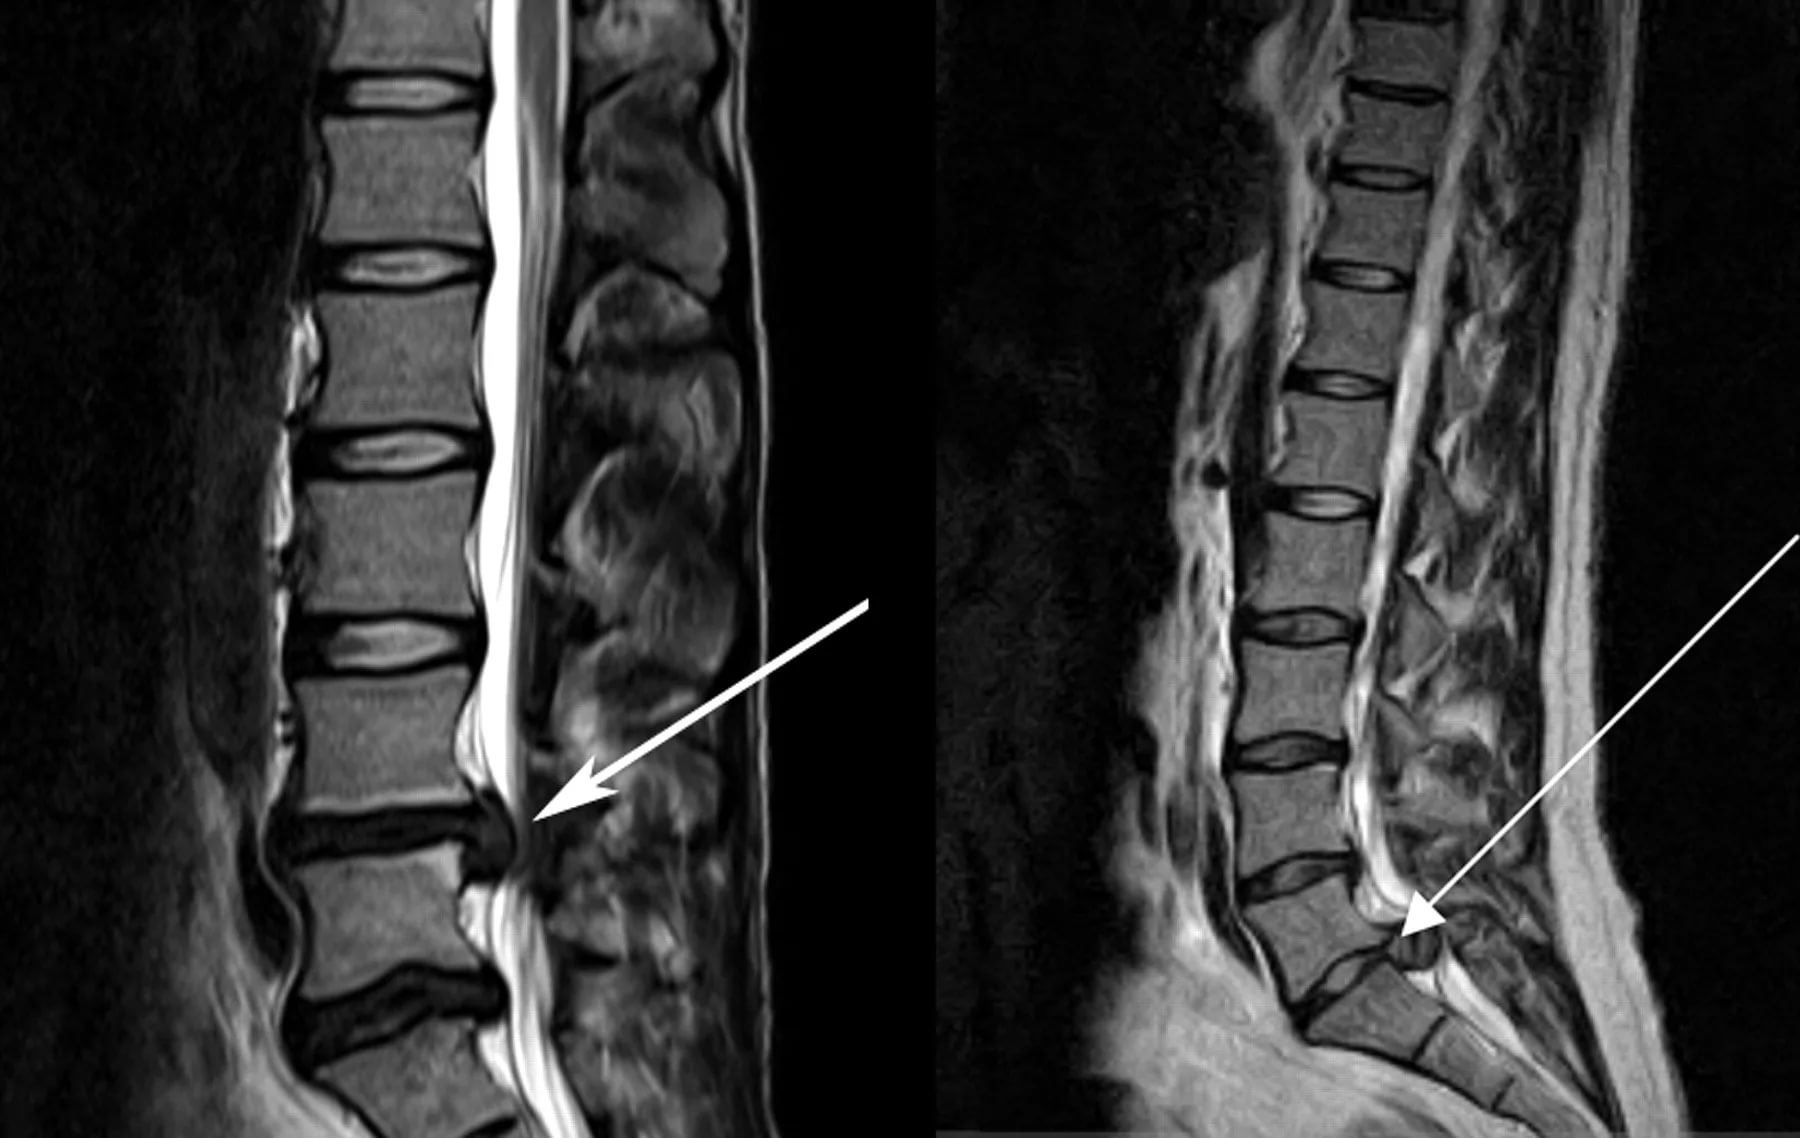

Боль при остеохондрозе или протрузии может отдавать в левую или правую половину спины

К патологическим причинам, по которым может болеть в пояснице слева сзади у женщины, относят заболевания позвоночника, яичника и маточных труб, а также некоторые проявления болезней ЖКТ, легких и даже сердца.

МРТ показывает состояние мягких тканей, костей и хрящей

Если женщина при появлении болей в пояснице с левой стороны займется выяснением причин, а не лечением в домашних условиях без постановки диагноза, последующая терапия окажется более результативной. Нужно обратиться к специалисту, который после опроса сможет дифференцировать патологию от других нарушений и дать направление на уточняющее обследование.

При подозрении на болезни сердца могут сделать ЭКГ, УЗИ сосудов. При патологиях позвоночника обязательно потребуется рентген. При разных нарушениях назначают МРТ, КТ, а также сдачу стандартных лабораторных анализов.